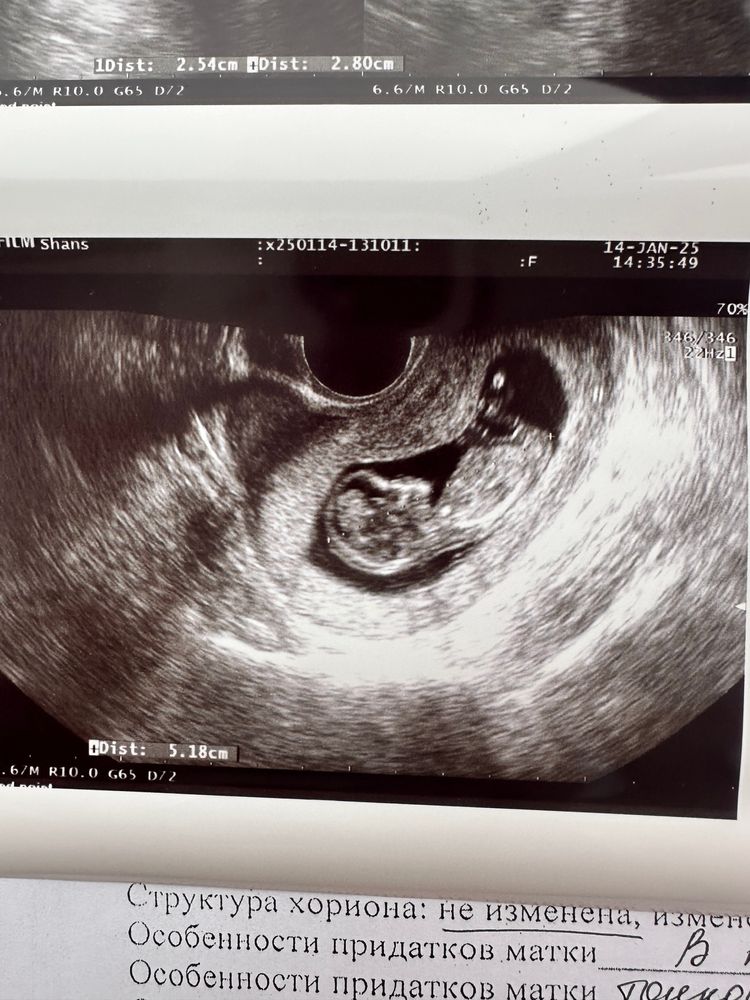

12 недель не визуализируется мочевой пузырь 😔

На 1 скрининг через 6 дней, очень надеюсь что все найдут 🙏🏻